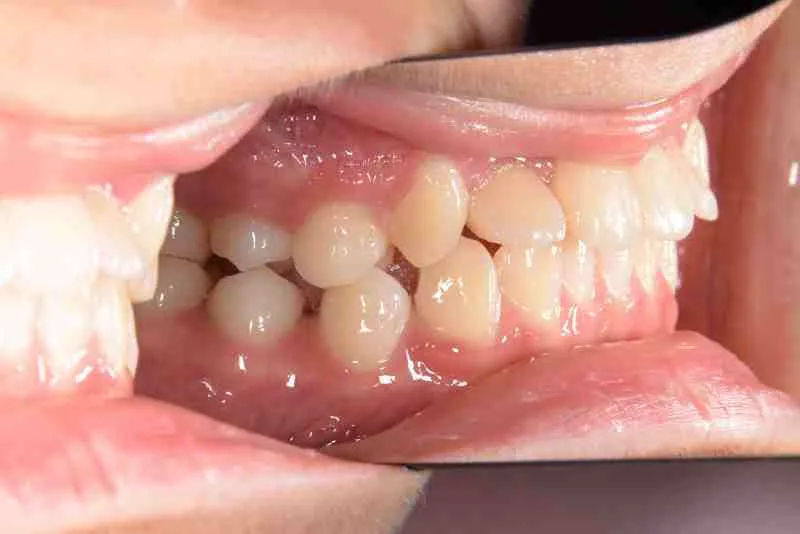

• 初診

初診時年齢 小学校2年生 (女性) 主訴 受け口・がたがた

診断名 埋伏歯・反対咬合・叢生 装置名

特徴 ゆがんで生えている

上の歯と下の歯で舌をはさむ癖がある

状態 永久歯が生える隙間がない(叢生)

受け口(下顎前突/反対咬合)

歯が埋まっている/歯がない(埋伏歯)

受け口で、ガタガタが有りました。

初診